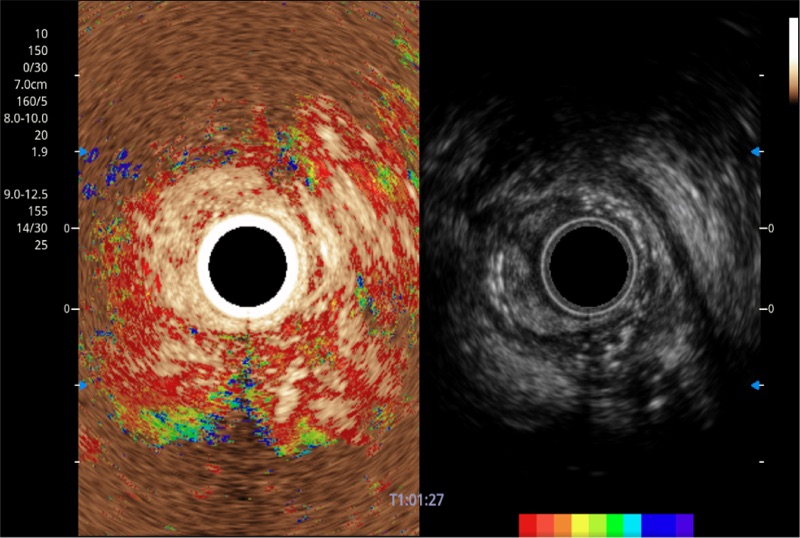

可人为将灰阶图像转变成彩色的显示方式,增强人眼对于不同回声强度的敏感度,主观上增加了图像分辨率

融合谐波技术

动态声压控制技术

TIC时间强度分析曲线

具有四种造影成像效果